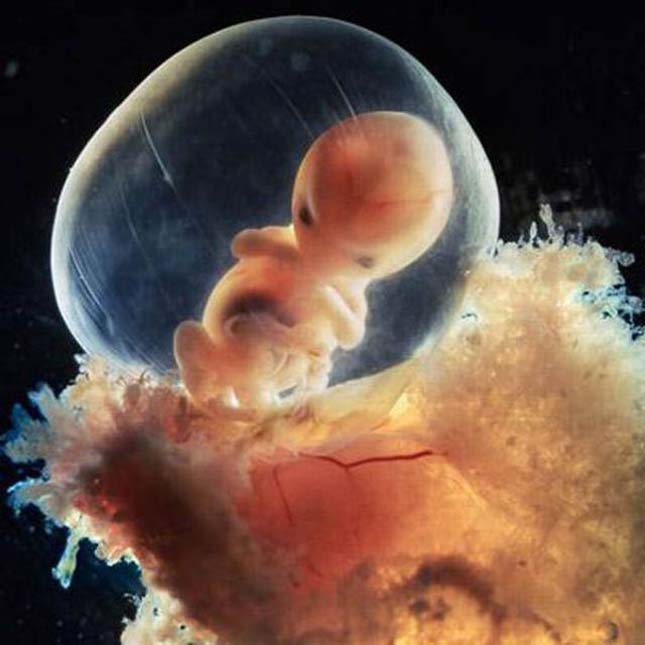

8. hét. A gyorsan fejlődő embrió védve van a magzati burokban.